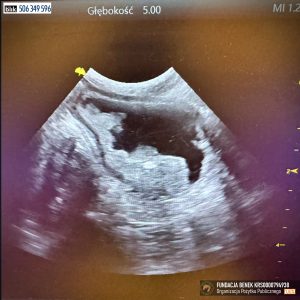

w obrazie usg typu a-fast – hiperechogenne, okrągłe zmiany w tkance wątrobowej – podejrzenie guzkowego rozrostu nienowotworowego wątroby – do potwierdzenia w badaniu FNA, zmiana w pęcherzu moczowym dosyć nieregularna o wymiarach ok. 2,5 x 1,3 cm, nerki o zatartej strukturze korowo-rdzennej poza tym brak odchyleń